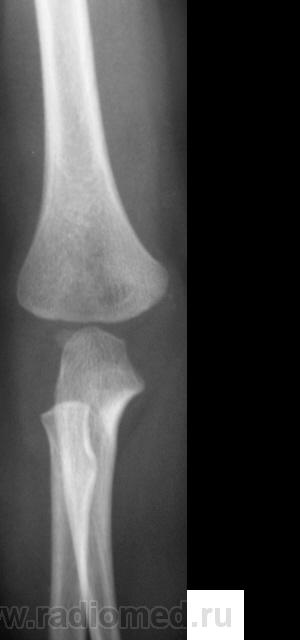

Травма.   Ребенок направлен на рентгенографию костей предплечья и локтевого сустава.

Поднадкостничный перелом в/3 лучевой кости.

А, что со средней третью?

Я думаю,что в с/3 нет перелома,скорее всего полосы просветления-тени сосудистых каналов,может я и не права.

Я думаю, норма. Смутила линия просветления в заднем отделе метафиза плечевой кости. Но жировые подушечки в норме. Думаю, нет костно-травматических изменений.

Я тоже не вижу патологии.